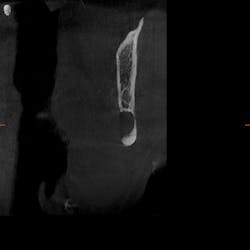

As part of our intake process to make a sleep mandibular advancement device, we take a cone beam image (figures 1–4). This way we can evaluate sinuses, septum, turbinates, teeth, and jaws.

Upon examination, it was noted that a dark, radiolucent lesion was present on the lower right jaw, anterior to the angle of the mandible. The patient didn’t have any pain, symptoms, or knowledge of the lesion. It was not palpable. He reported that he had his third molars removed in his twenties with no complications.